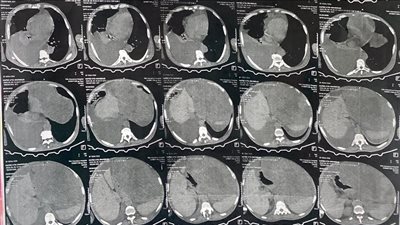

إنقاذ مريض بعد استئصال ورم وزنه 15 كجم بمستشفى النيل للتأمين الصحي بالقليوبية